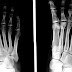

The second metatarsal bone is a long bone in the foot. It is the longest of the metatarsal bones, being prolonged backward and held firmly into the recess formed by the three cuneiform bones. The second metatarsal forms joints with the second proximal phalanx (a bone in the second toe) through the metatarsophalangeal joint, the cuneiform bones, third metatarsal and occasionally the first metatarsal bone.

Like the four other metatarsal bones, it can be divided into three parts: base, body and head. The base is the part closest to the ankle and the head is closest to the big toe. The narrowed part in the middle is referred to as the body of the bone. The bone is somewhat flattened, giving it two sides: the plantar (towards the sole of the foot) and the dorsal side (the area facing upwards while standing).

It presents four articular surfaces: one behind, of a triangular form, for articulation with the intermediate cuneiform bone; one at the upper part of its medial surface, for articulation with the medial cuneiform; and two on its lateral surface, an upper and lower, separated by a rough non-articular interval. Each of these lateral articular surfaces is divided into two by a vertical ridge: the two anterior facets articulate with the third metatarsal and the two posterior (sometimes continuous) with the lateral cuneiform. A fifth facet is occasionally present for articulation with the first metatarsal; it is oval in shape, and is situated on the medial side of the body near the base.